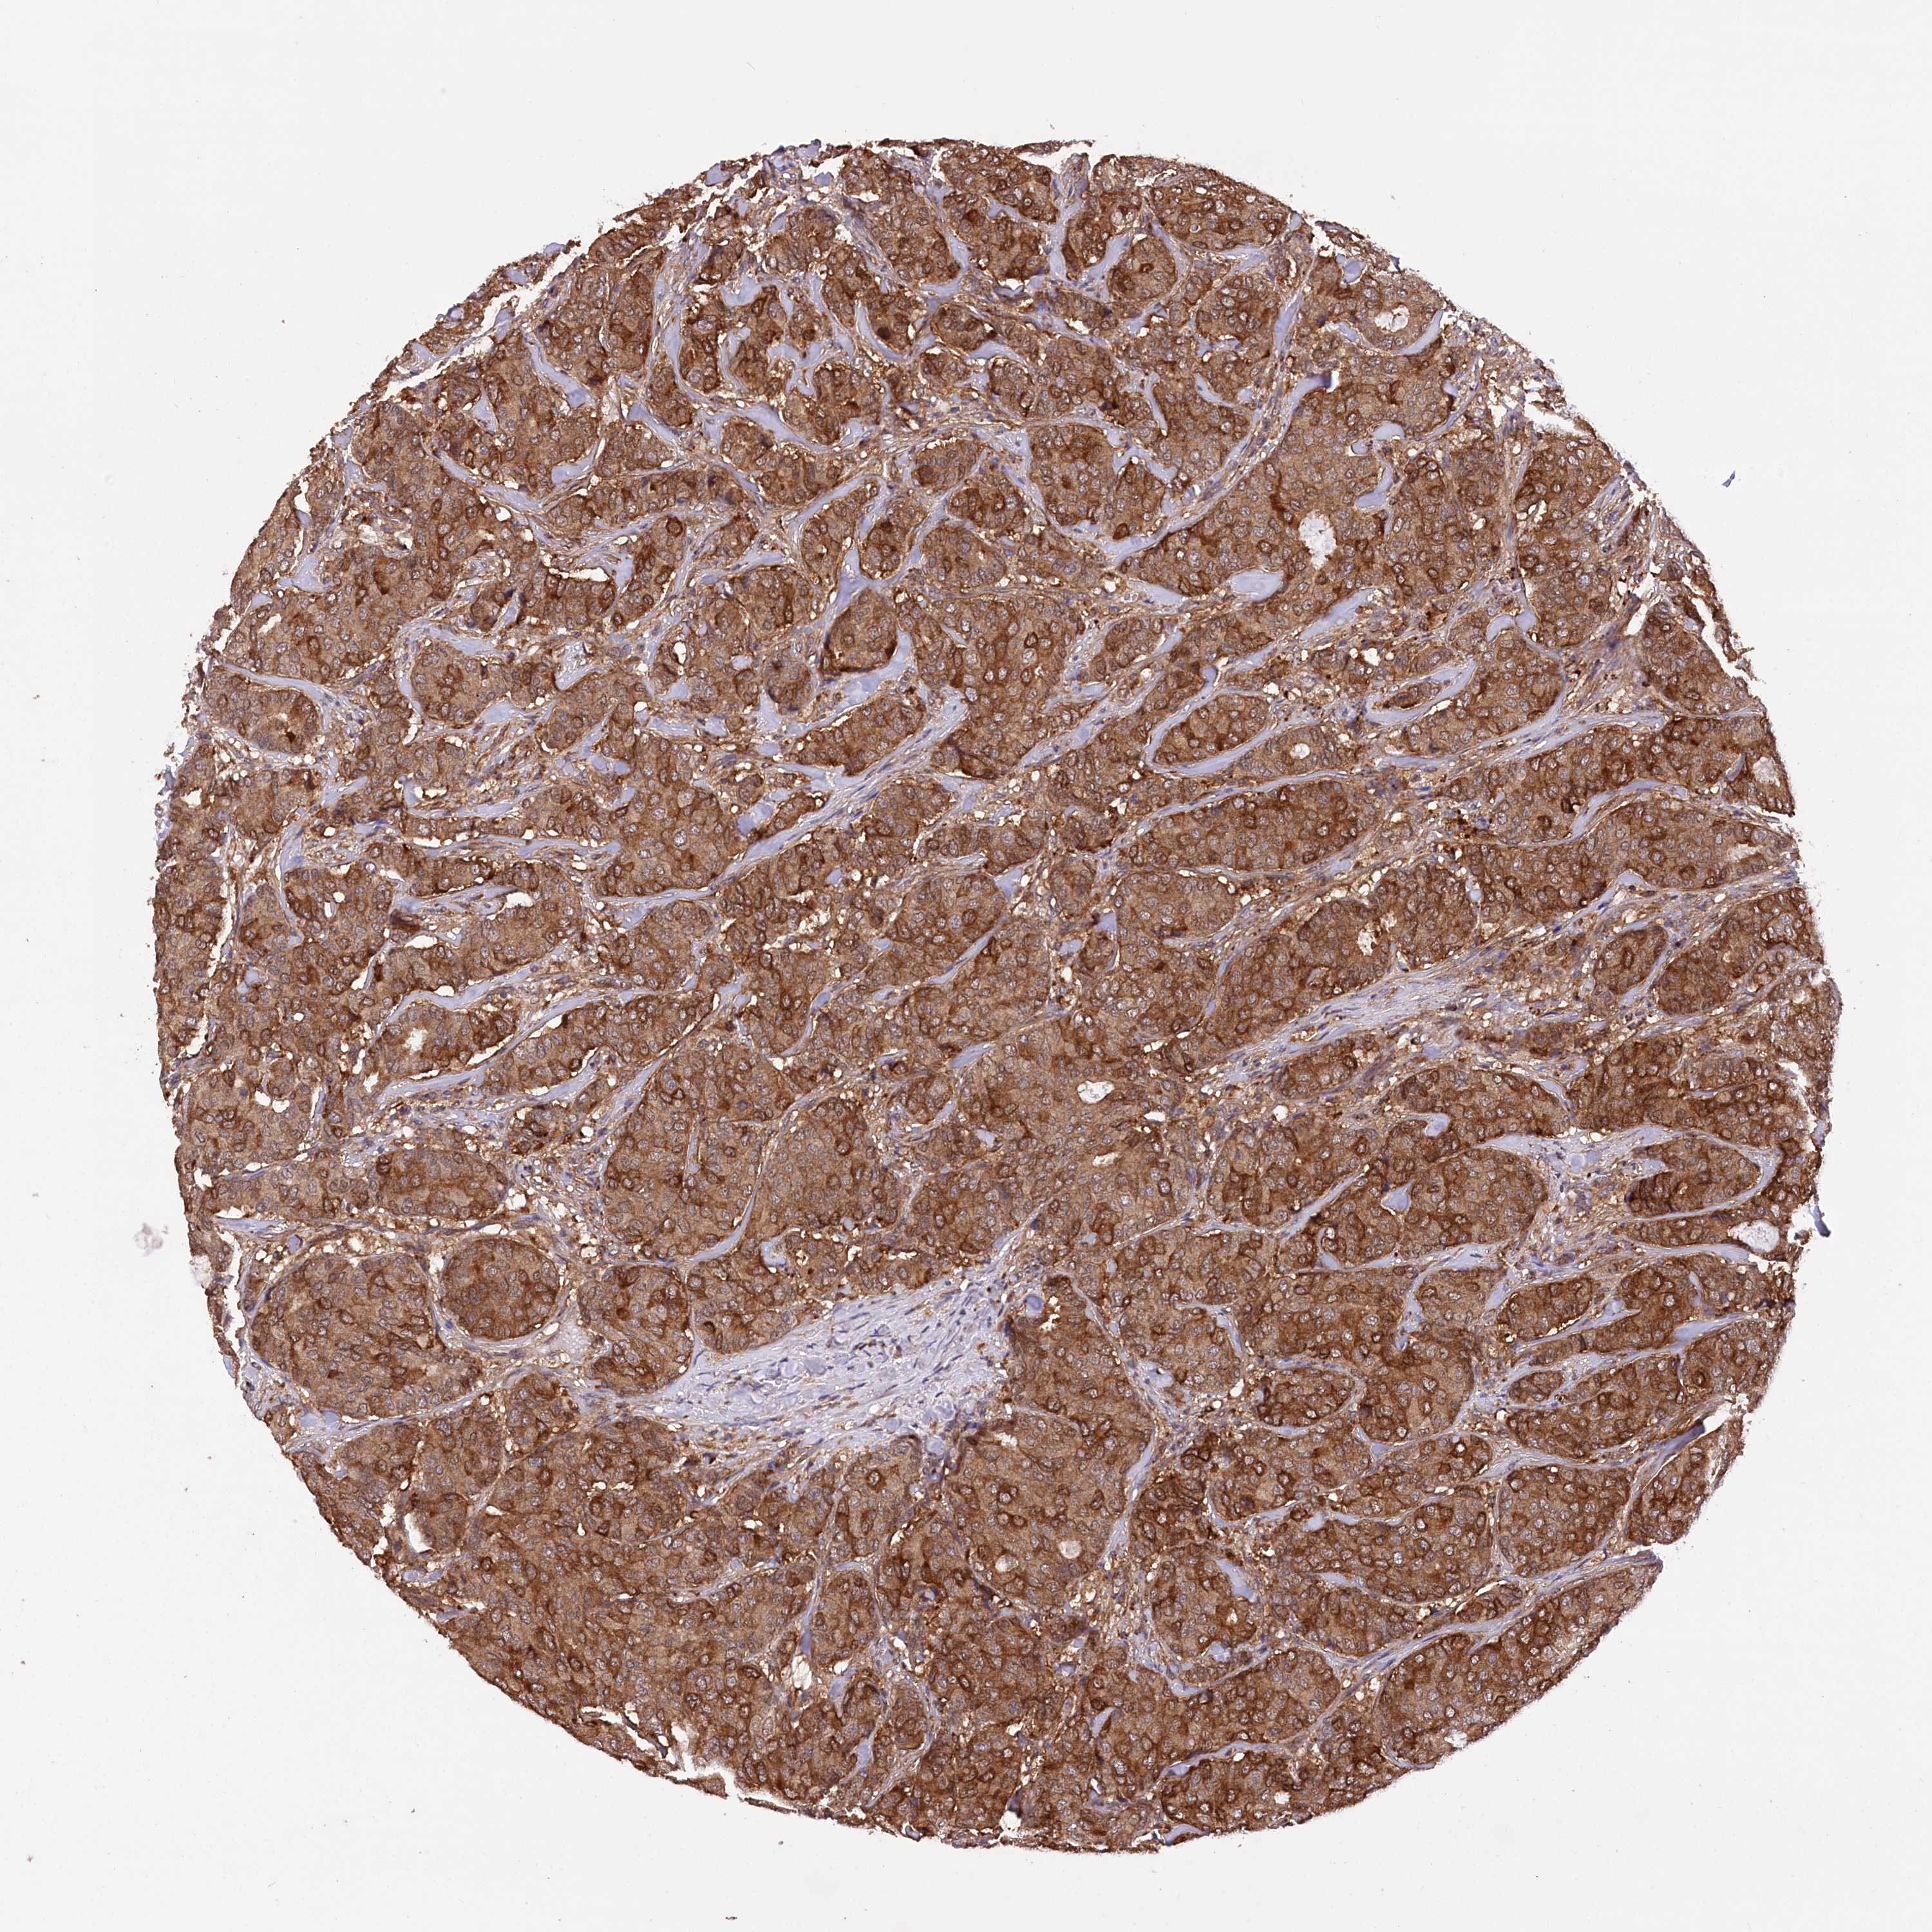

BRCA TCGA BRCA VALIDATION PROTEIN EXPRESSION